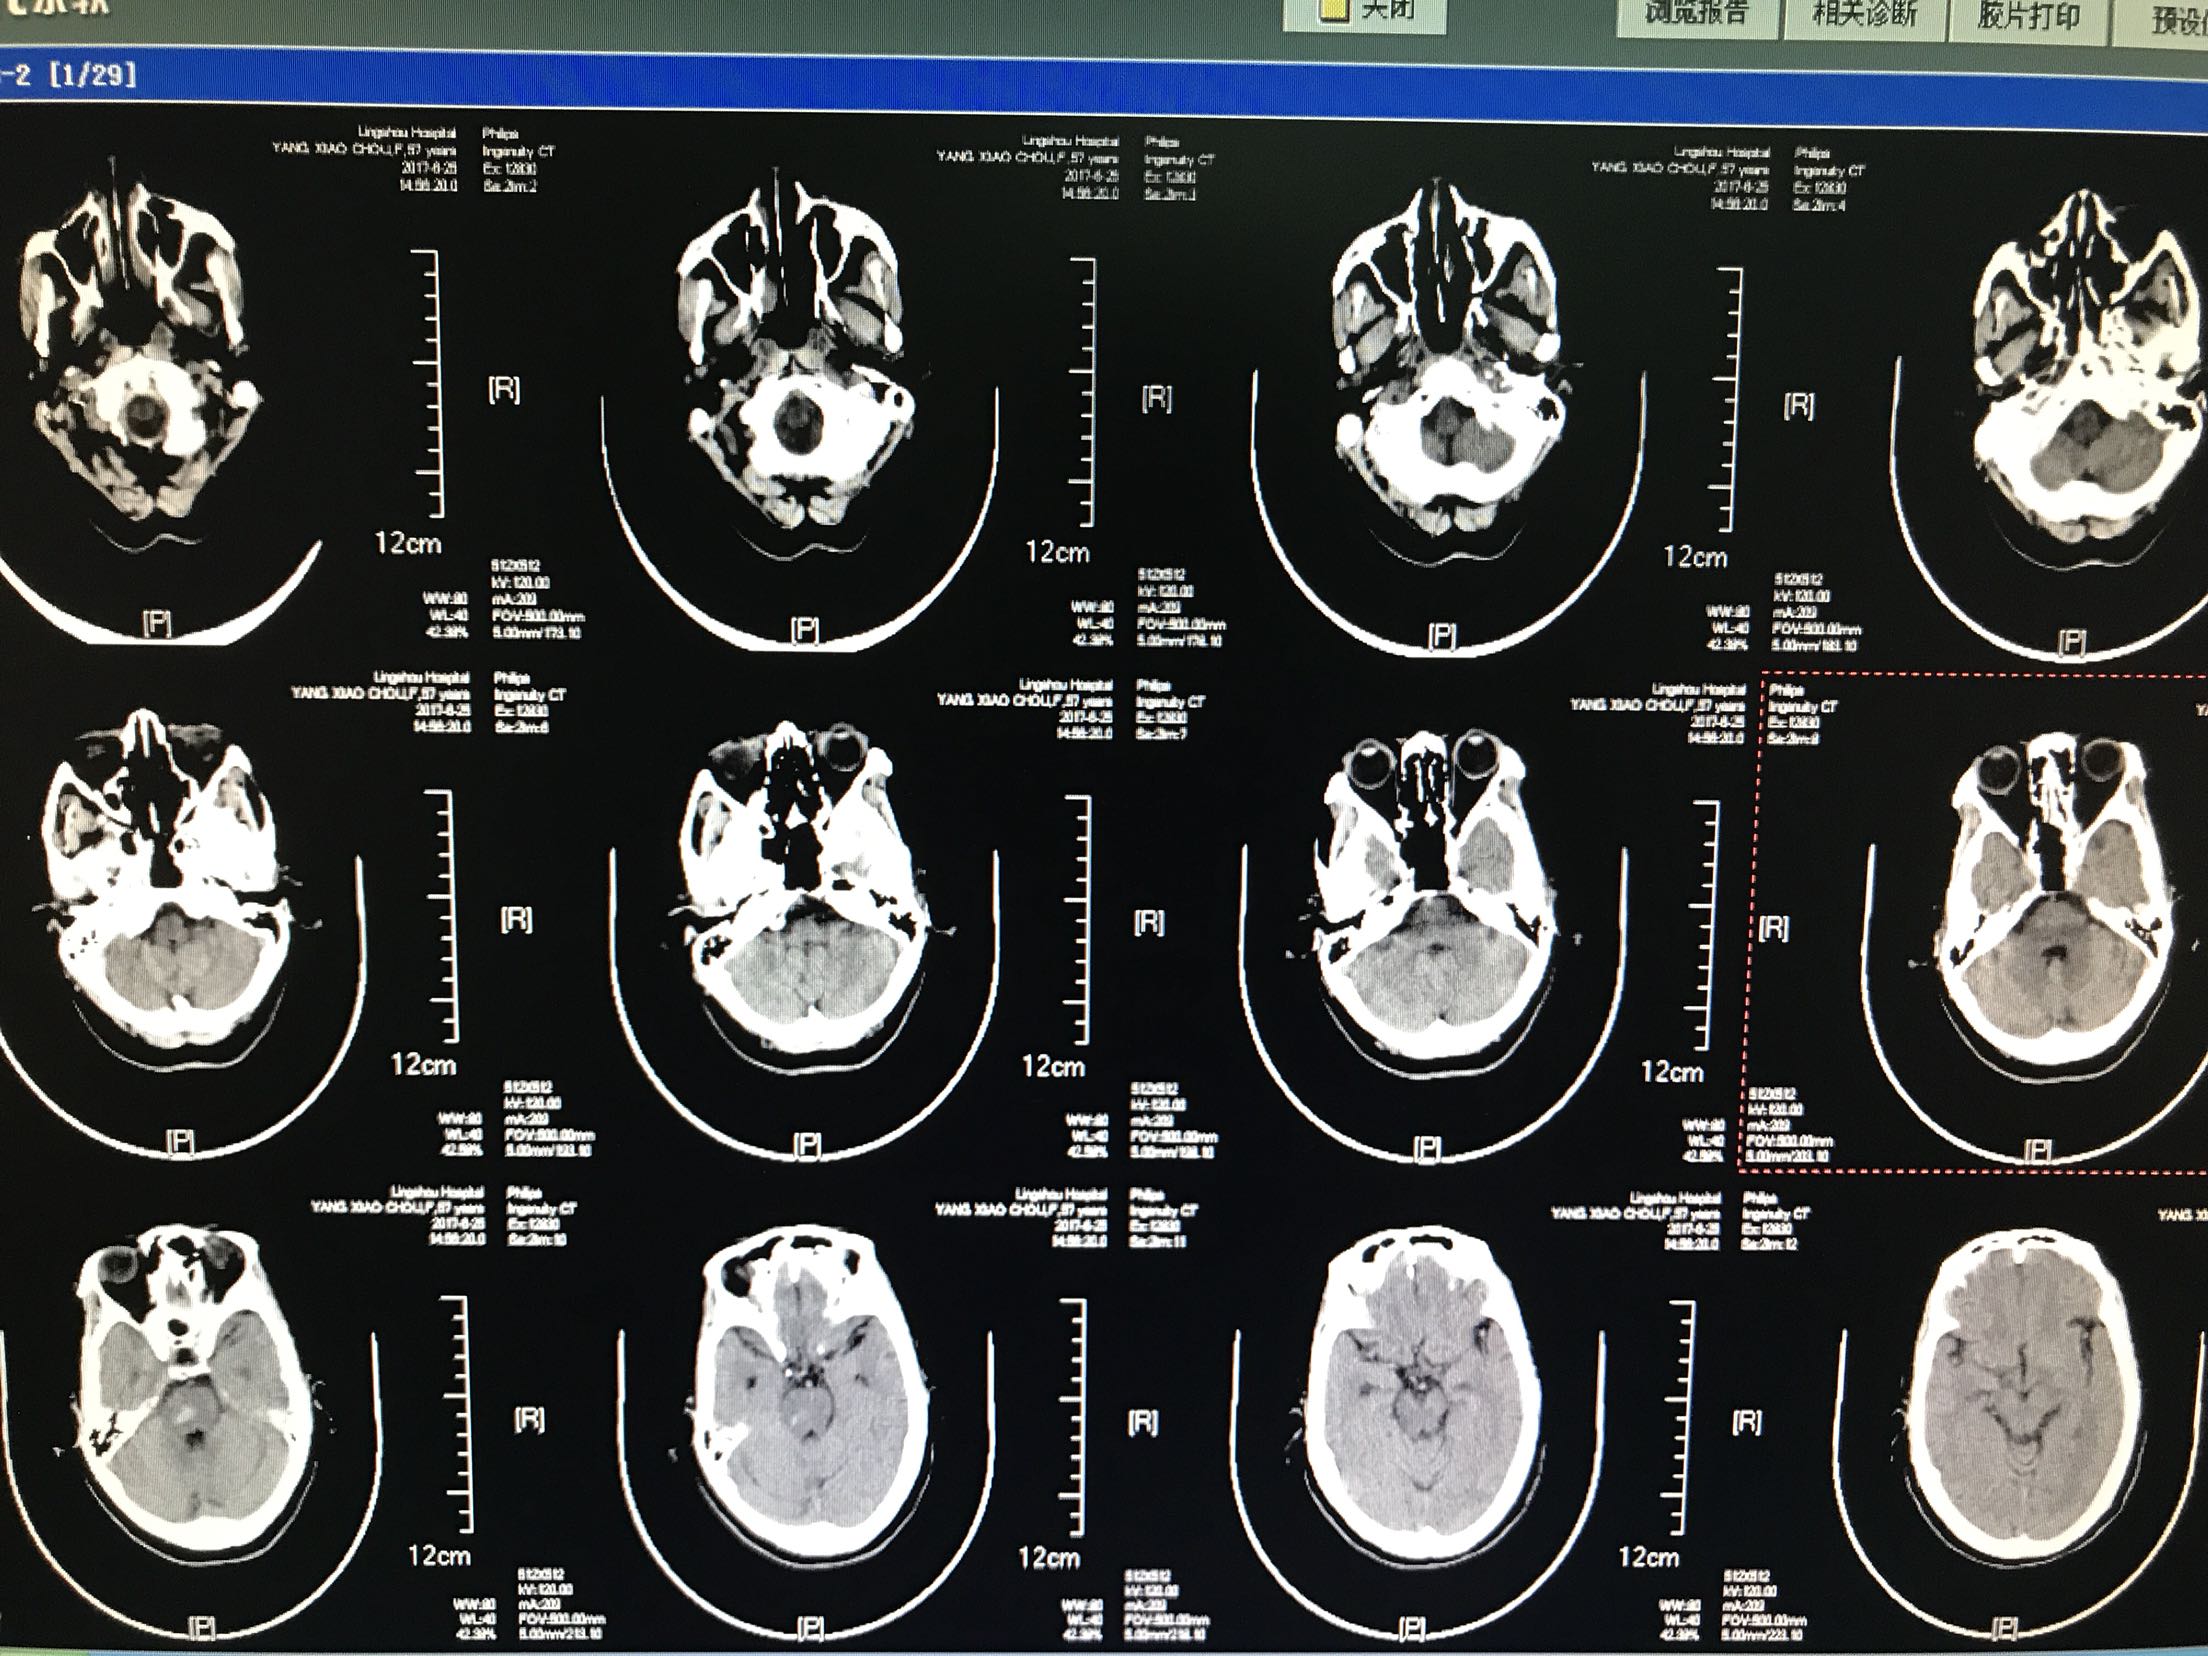

患者主因言语不利,右侧肢体无力2小时入院,患者中年男性57岁,既往"高血压,脑梗死"病史,未留明显后遗症,未监测血压,患者入院前2小时无明显诱因出现言语不利,右侧肢体无力,听理解无障碍,上肢不能抬举,下肢不能负重,伴左侧头痛,无头晕,恶心,呕吐,无饮水呛咳,急诊急查头CT:脑干出血,心电图示:房颤,为进一步治疗收住院

体温36.9℃ 脉搏50次/分 血压159/90mmhg,神清,运动性失语,伸舌右偏,双肺呼吸音清,未闻及干湿性啰音,心音有力各瓣膜听诊区未闻及杂音,腹软肝脾未触及,肠鸣音正常,双下肢无水肿,左侧上下肢肌力肌张力正常,右侧上下肢肌力0级,肌张力高,双侧巴氏征阳性

1.脑干出血2.房颤,药物给于止血,脱水降颅压等治疗,密切观察意识变化